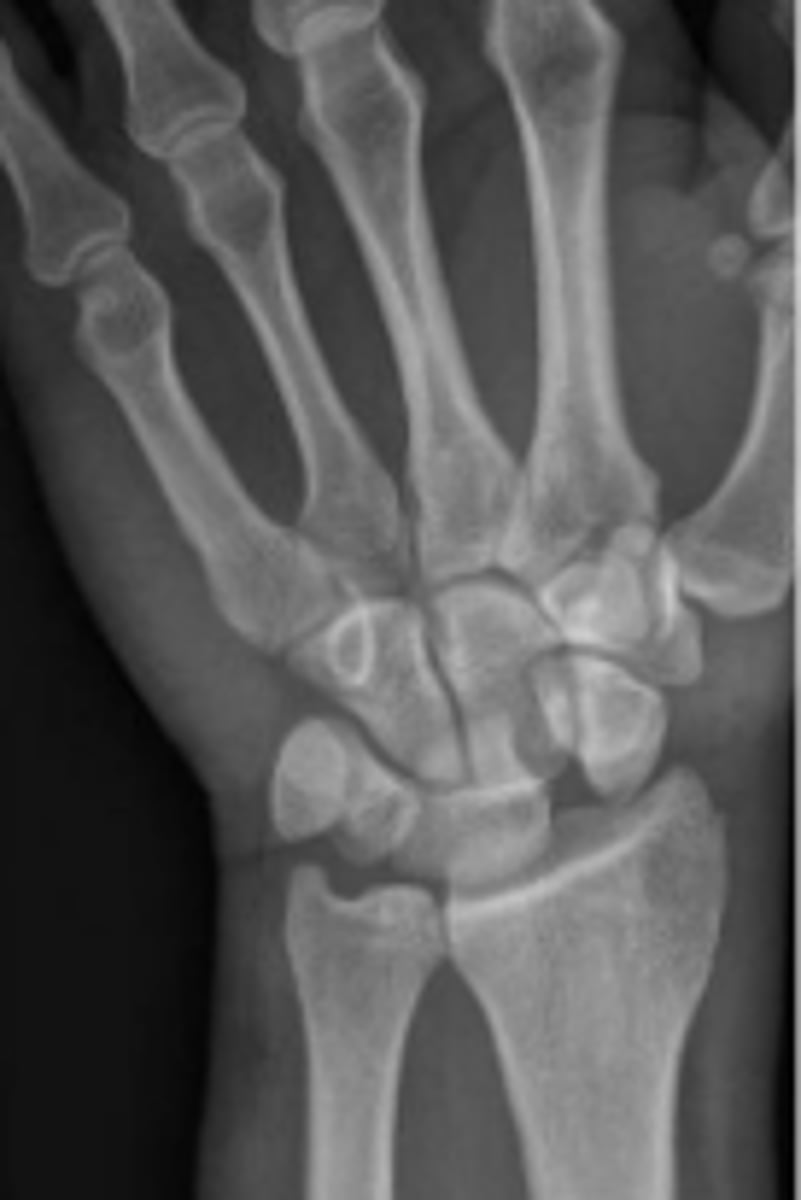

Medial oblique of the right wrist

What is the name of the radiographic view?

Right triquetrum

What are the arrows pointing to?

Right 1st metacarpal bone

What is outlined?

Right pisiform

Right radiocarpal joint

What joint space are the arrows pointing to?

Right 1st metacarpophalangeal joint

What joint space are the arrows pointing to

Hook of the right hamate

Right lunate

Right hamate

Base of the 2nd right metacarpal bone

What is the arrow pointing to?